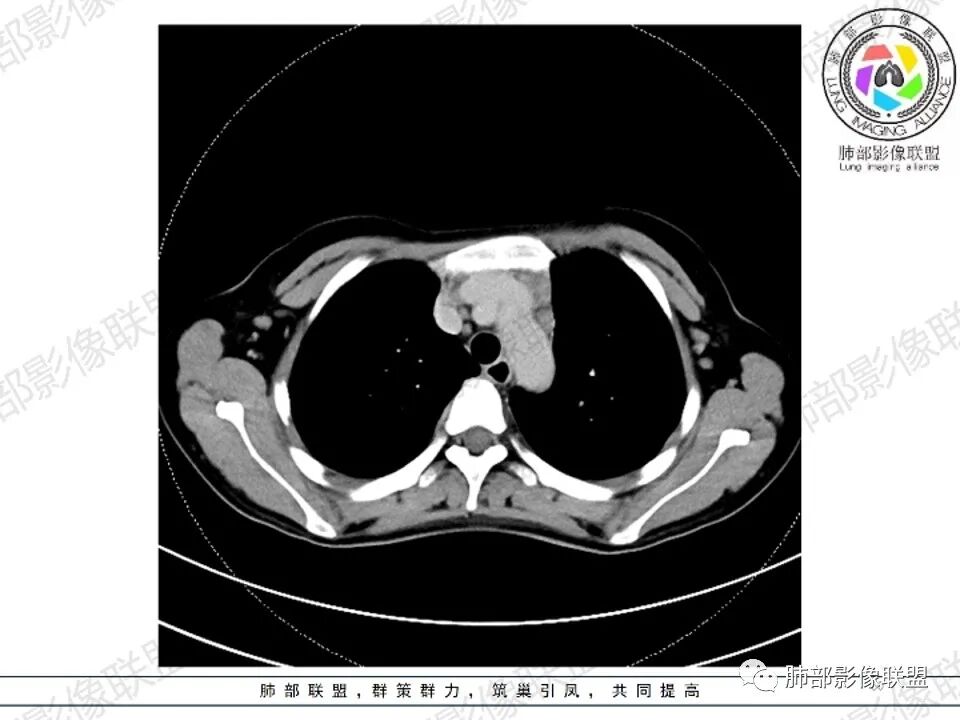

2.影像显示前纵隔不规则块状影,依势贴附心脏大血管旁,密度不均,边界不甚清楚,有结节融合感。

3.病灶轻度不均匀强化,可见血管穿行,散在液性低密度区。

双肺门未见肿大淋巴结。

4.双侧腋窝区见增大淋巴结,边界清楚。

1.年轻女性,前纵隔不规则块状影,密度不均,边界不甚清楚,有结节融合感,轻度不均匀强化,可见血管穿行,最常见最符合的无疑是淋巴瘤!